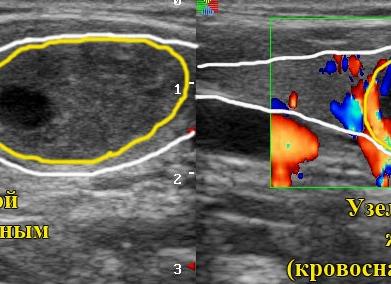

Одним из наиболее достоверных методов определения гиперплазии щитовидной железы является ультразвуковая диагностика. Именно при ней по ряду ЭХО признаков можно выявить изменения в щитовидной железе.

Помогают диагностировать патологию эхопризнаки гиперплазии щитовидной железы на УЗИ. На начальных этапах её развития разрастающиеся клетки уже иначе реагируют на сигнал ультразвукового датчика, чем здоровые. При диффузной форме признаки изменяющихся клеток обнаруживаются распространённо по всему органу (или доле). Если дополнительно образуются узлы, ЭХО сигнал отображает локальные участки их местонахождения и позволяет выяснить их размер, форму, структуру, очерченность.

- УЗИ. При очевидном увеличении левой или правой доли органа проводят ультразвуковое исследование. Если в железе обнаруживаются узлы диаметром от 10 мм, делают пункционную биопсию.